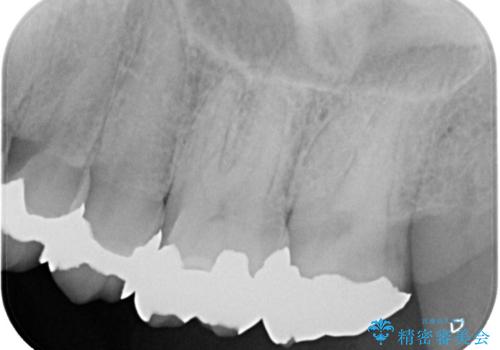

保険適用のメタルインレーと歯質の境目にう窩ができており、補綴物のやり替えとなりなした。

メタルインレーを除去したところう窩が深く、遠心の健歯質が歯肉縁下深くに位置したためディスタルウェッジ術を行い骨と歯肉の高さを下げた上で補綴しています。

元々インレーが入っていましたが、残存歯質量が少なく破折のリスクを説明しジルコニアクラウンでのやり替えとなりました。